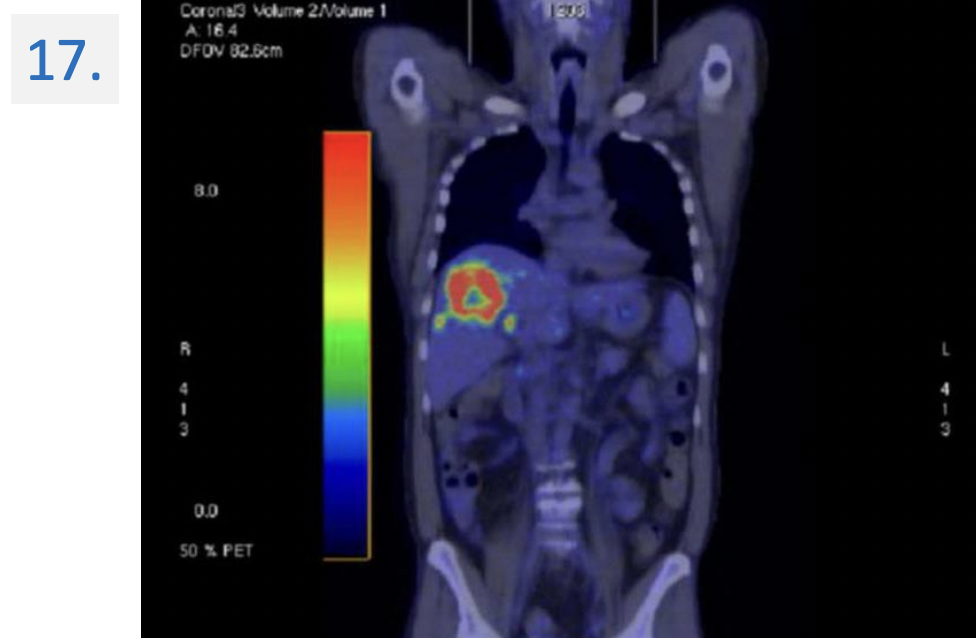

Modality:

FDG PET-CT (right panel: non-contrast CT) → 18(F)-fluoro-deoxy-glucose

Region:

upper abdomen, axial view

Diagnosis:

Malignant tumor → colorectal cc. metastasis → liver